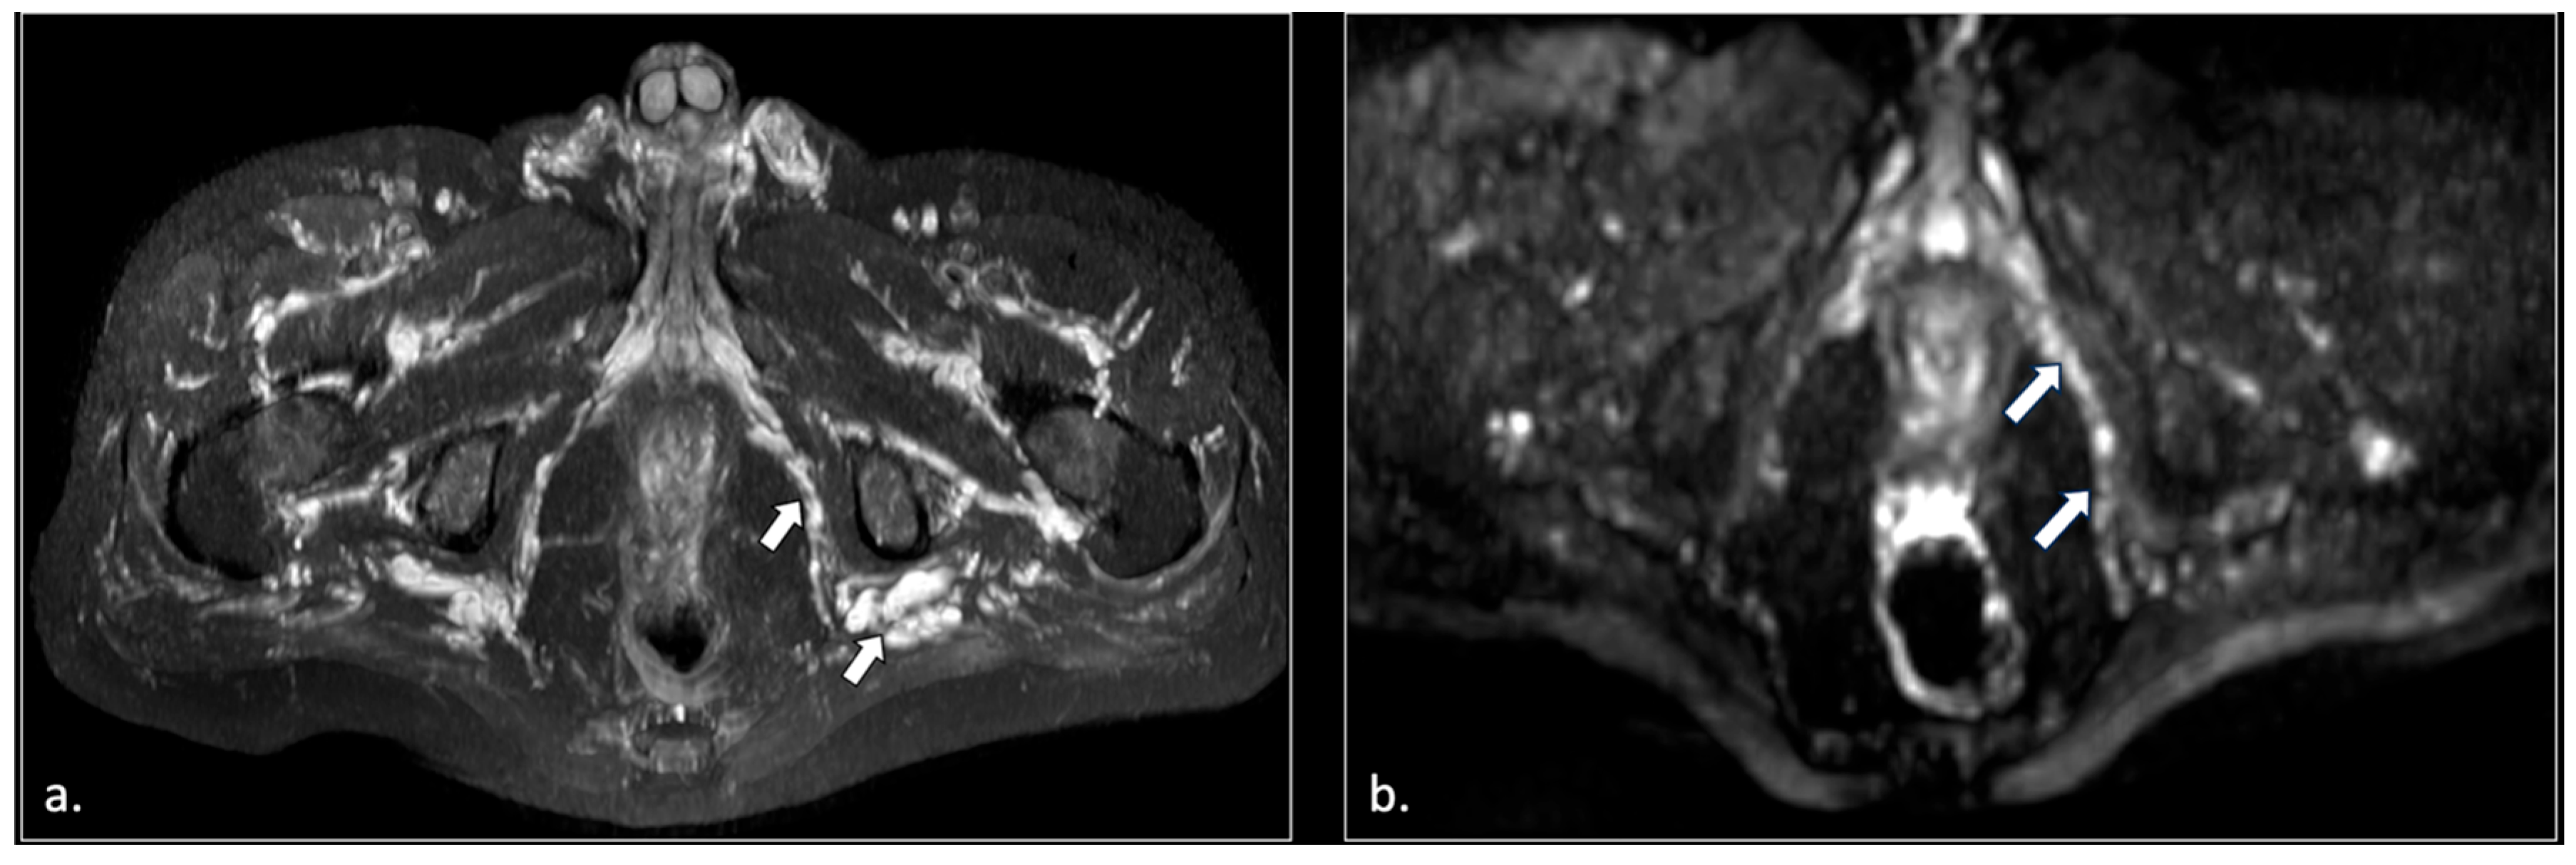

- Unilateral or bilateral hypertrophy of the pyriform muscle (4 patients);

- Unilateral or bilateral lesions of the sacrotuberous and/or sacrospinous ligaments (interligamentous space) (5 patients);

- Unilateral rupture of puborectal and/or pubococcygeal muscle (4 patients);